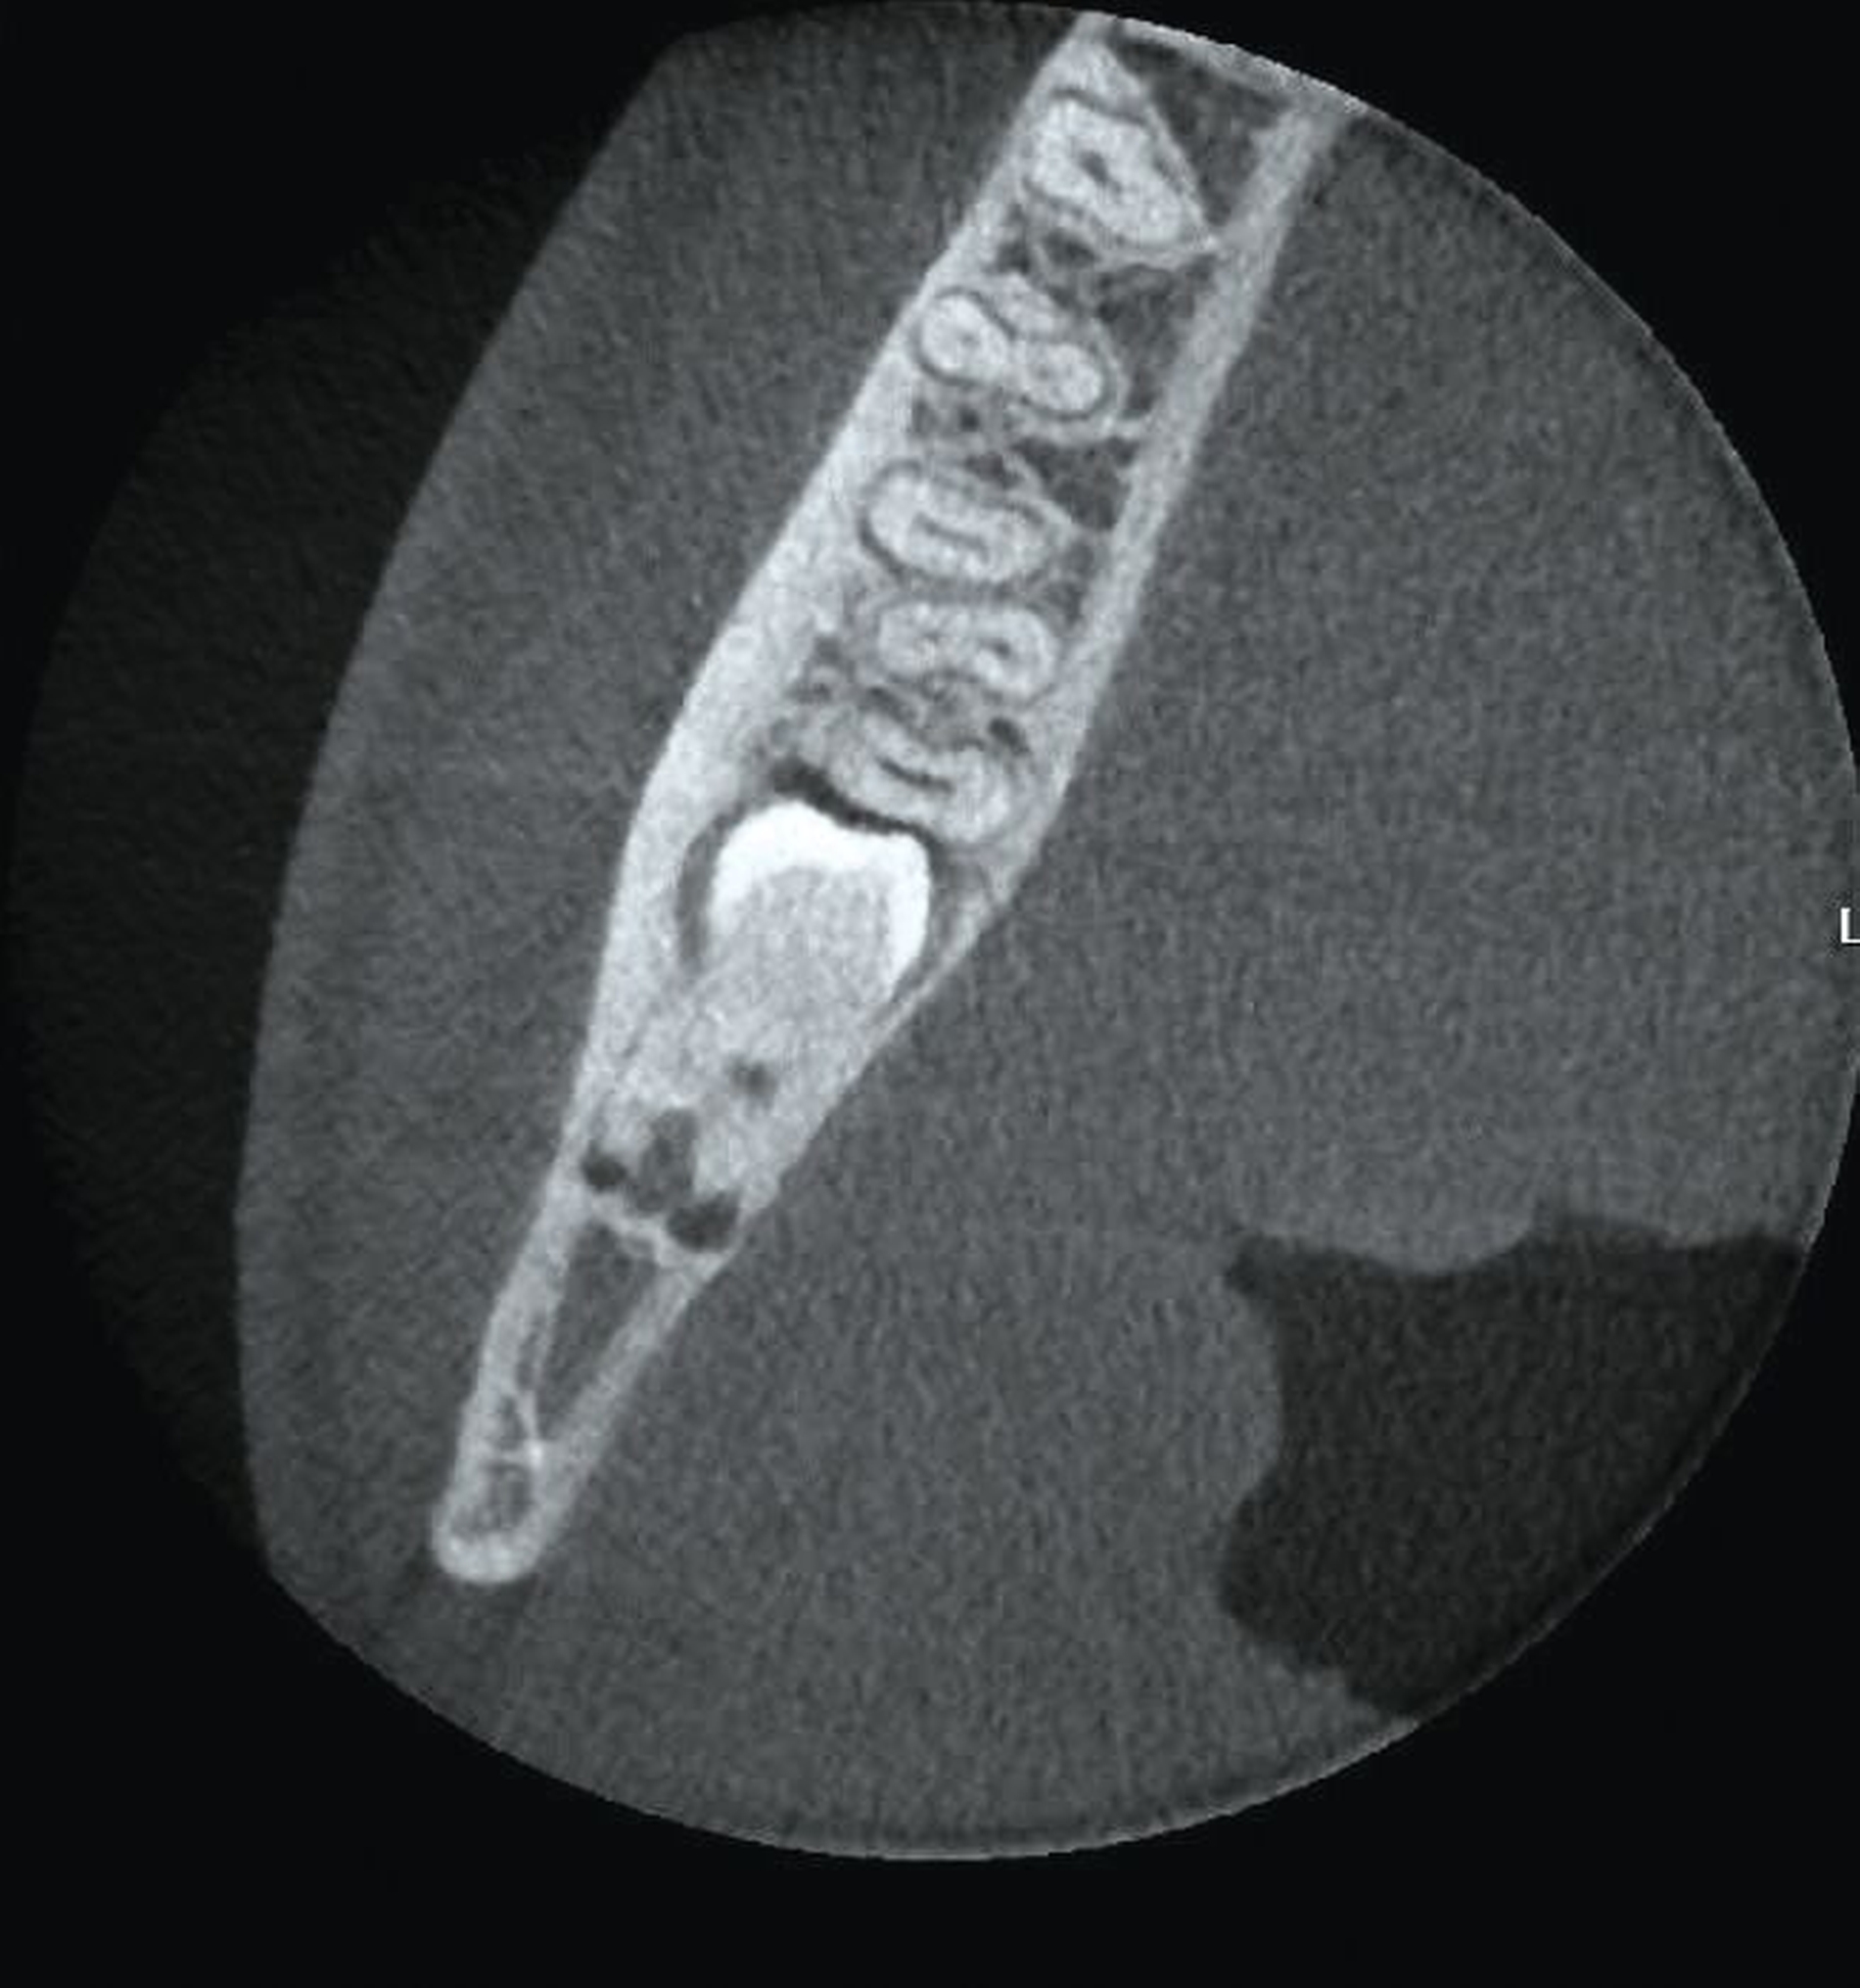

Im Unterkiefer linksseitig zeigt sich der Canalis mandibularis lingual verlaufend, in enger Lagebeziehung zur Wurzel des retinierten und ebenfalls nach mesial gekippten Zahnes 38 (Abbildung 3).